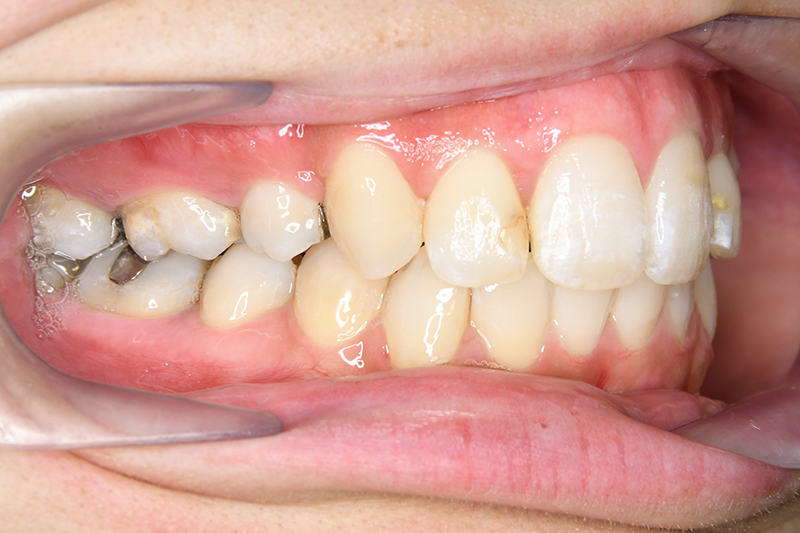

初診時

FP・IOP

口腔内所見 over jet 11.5mm、over bite 5.5mm、右側臼歯関係Full ClassⅡ級、左側end onⅡ級、上顎顎歯列はテーパー型であり、上顎中切歯は押し出されるように大きく唇側傾斜していた。下顎前歯部は叢生を呈しており、左下5は歯冠長が短く半埋伏していた。